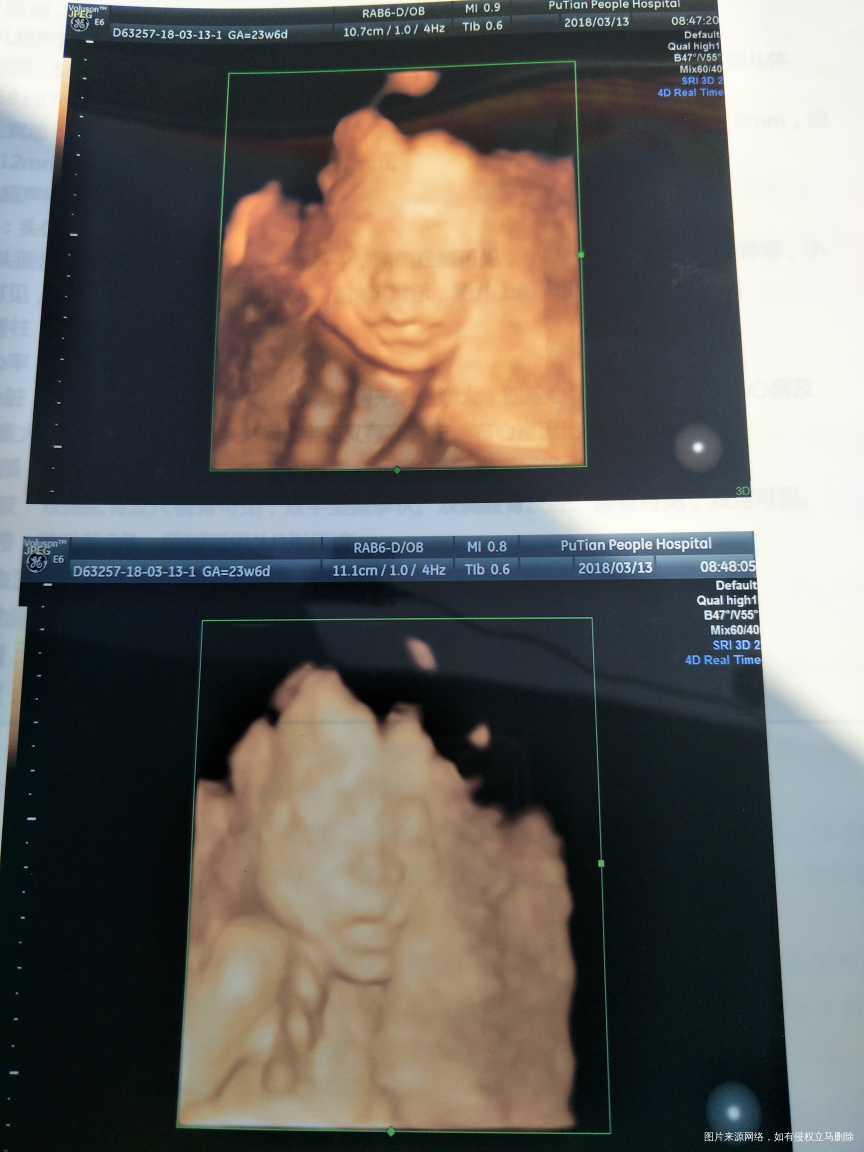

7个月了,想给宝宝准备买衣服了,可是愁,不知道是男孩女孩,很难买……能否通过四维帮我看看是男孩女孩

你好,你的四维报告提示胎儿正常,脐绕颈一周有可能还能绕回来,不要看是男是女,关键是生一个健康的宝宝

四维彩超提示胎儿发育正常,保持好心情。